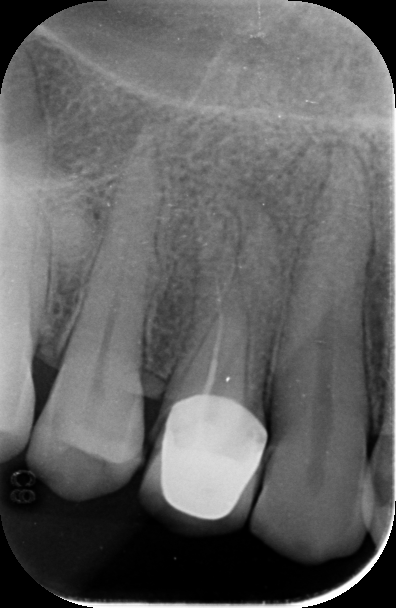

Upon examination, it was noted that the crown was improperly placed with faulty cementation; however, this was unlikely the primary cause of the severe pain. Radiographic analysis revealed a critical oversight during the initial root canal treatment: the premolar tooth had two root canals, but only one canal was partially filled, and the second canal was completely untreated. The filled canal was only obturated halfway, leaving the apical portion unsealed, which is a common source of persistent infection and pain.

The crown was removed using high-speed carbide burs, and the old filling was cleared. Both canals were thoroughly cleaned and filled to the apex, followed by composite buildup. The patient was recalled after three days for new crown placement and reported complete pain relief, no longer requiring any medication.